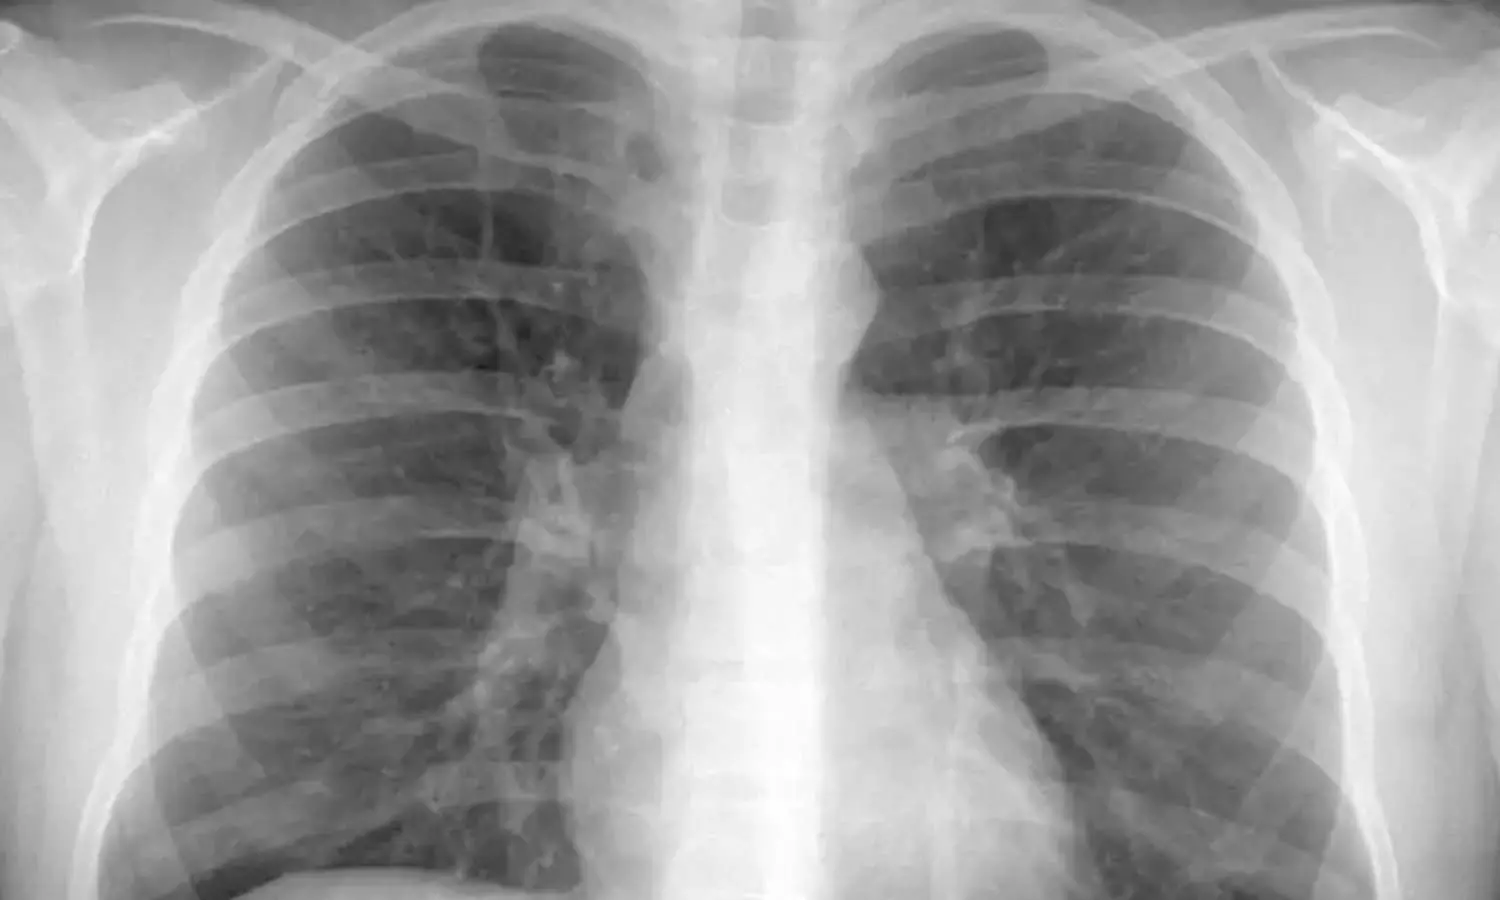

കോവിഡിന്റെ പ്രധാനലക്ഷണങ്ങളിൽ ഒന്നാണ് ശ്വാസതടസം. കോവിഡിനെ അതിജീവിച്ചവരിൽ ശ്വാസംമുട്ടൽ വിട്ടുമാറാത്തത് ഇപ്പോഴും വൈറസിന്റെ ലക്ഷണങ്ങൾ ഉള്ളിലുള്ളത് കൊണ്ടുതന്നെയാണ്. ഏറെ നാൾ കഴിഞ്ഞിട്ടും ശ്വാസതടസം മാറുന്നില്ലെങ്കിൽ സമഗ്രമായ ഹൃദയ, ശ്വാസകോശ പരിശോധനകൾ നടത്തണം. പൾമണറി ഫംഗ്ഷൻ ടെസ്റ്റുകൾ, എക്കോകാർഡിയോഗ്രാം, ചെസ്റ്റ് എക്സ്റേ, അല്ലെങ്കിൽ സ്റ്റാൻഡേർഡ് ആക്റ്റിവിറ്റി ടെസ്റ്റുകൾ എന്നിവയാണ് ഇതിന് സഹായിക്കുക.